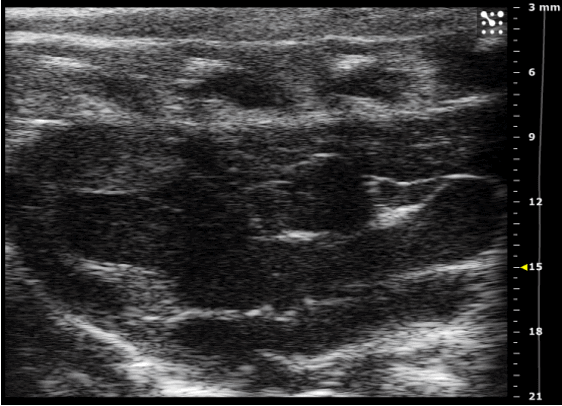

L’échographie est une imagerie basée sur le principe de la réflexion des ondes ultrasonores. Ainsi, la sonde ou transducteur émet des ultrasons qui rencontrent les organes, les liquides ou les structures internes. Une partie des ondes est réfléchie vers le transducteur, selon la densité et la nature des tissus traversés. Une analyse du temps mis par les ondes pour revenir et de leur intensité permet de reconstruire une image en temps réel. Les zones de densité différente (os, liquides, tissus mous) apparaissent en niveaux de gris ou en couleur. Le doppler, sur le même principe, permet de détecter et quantifier la vitesse des structures en mouvement et donc d’étudier les flux sanguins. De la fréquence des ondes émises dépendent la résolution de l’image reconstruite et la profondeur de l’exploration. Il existe donc différentes sondes adaptées aux différents organes/modèles.

La plateforme GAIA est équipée d’un système d’imagerie ultrasonore de dernière génération (Vevo F2 FUJIFILM VisualSonics), de haute résolution, qui combine ultra-hautes et basses fréquences pour une imagerie par ultrasons permettant de collecter des données anatomiques, fonctionnelles et potentiellement moléculaires. Cet appareil permet entre autres les examens sur modèles murins d’échographie tels que l’évaluation de la fraction d’éjection cardiaque en TM ou mode B, le doppler vasculaire, le Strain Rate ou l’échographie de stress (réserve coronaire), avec en plus grâce à la plateforme de manipulation associée la possibilité de suivre la respiratoire et la fréquence cardiaque (ECG) et d’assurer leur synchronisation aux images ("gating") ; mais également la détection de tumeurs (moteur 3D disponible) ou la caractérisation de la vascularisation tumorale (échographie de contraste).